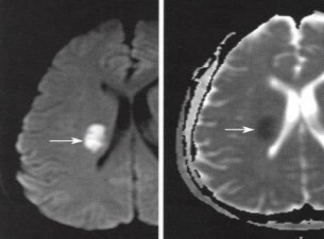

●急性缺血性脑卒中静脉溶栓术

急性缺血性脑卒中(AIS以下简称卒中)是当今世界危害人类生命健康、导致人类死亡的3大主要疾病之一,其发病率高、复发率高、死亡率高、致残率高。卒中在恢复脑灌注之前,每一分钟将会死亡190万个神经元、140亿个神经突触,一旦发生缺血性脑卒中,就必须争分夺秒,树立时间就是大脑的观念。目前世界公认的对于急性缺血性卒中,再灌注治疗是降低患者致残率和致死率的唯一有效手段,而静脉溶栓治疗是恢复脑血流灌注的最重要措施。

优点:静脉溶栓治疗可以使闭塞血管再通,恢复脑血流,挽救缺血性半暗带,最终降低患者致残率和致死率,是目前世界上公认的最好的有效手段,据大数据统计,符合静脉溶栓的病例接受了静脉溶栓的病例约67%获益。